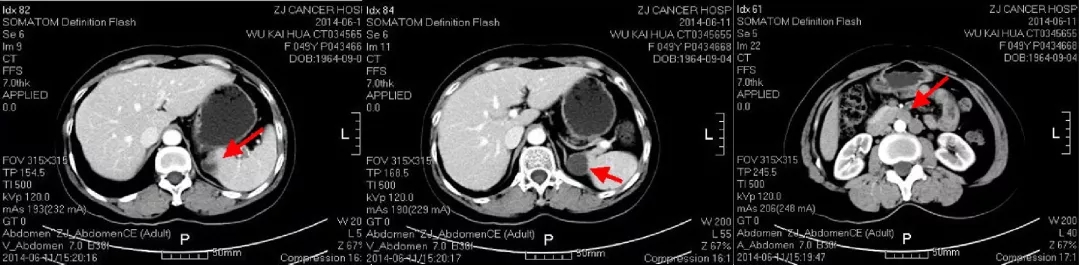

2014.6.11 CT:脾周囊性低密度灶2.4*2.7cm,较2014.2.26增大,腹主动脉旁肿大淋巴结,考虑“卵巢癌复发”。

CT检查结果